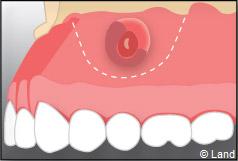

Une anesthésie et une incision semi lunaire sont réalisées et le lambeau de gencive est récliné.

Il faut localiser le bout de la racine de la dent atteinte, procéder au décollement de la lésion avec une curette à bords tranchants, couper et enlever la partie de racine infectée.

Une préparation de l’extrémité restante est effectuée à l’aide d’une petite fraise boule, de façon à recevoir une obturation canalaire étanche.